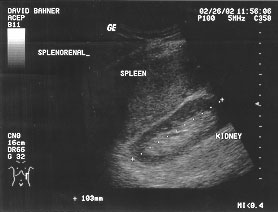

Splenorenal space (labeled)